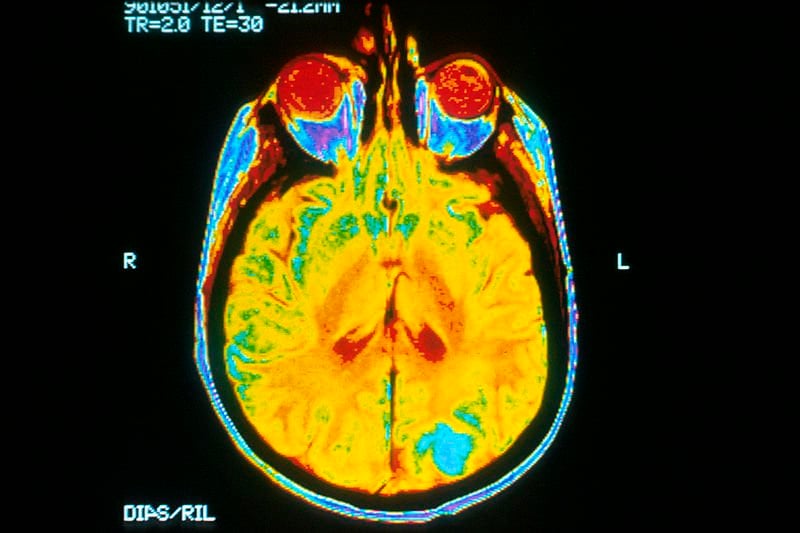

Image Source: The MRI brain cancer image is credited to Dr. Leon Kaufman. University Of California, San Francisco, NCI/NIH and is available in the public domain.